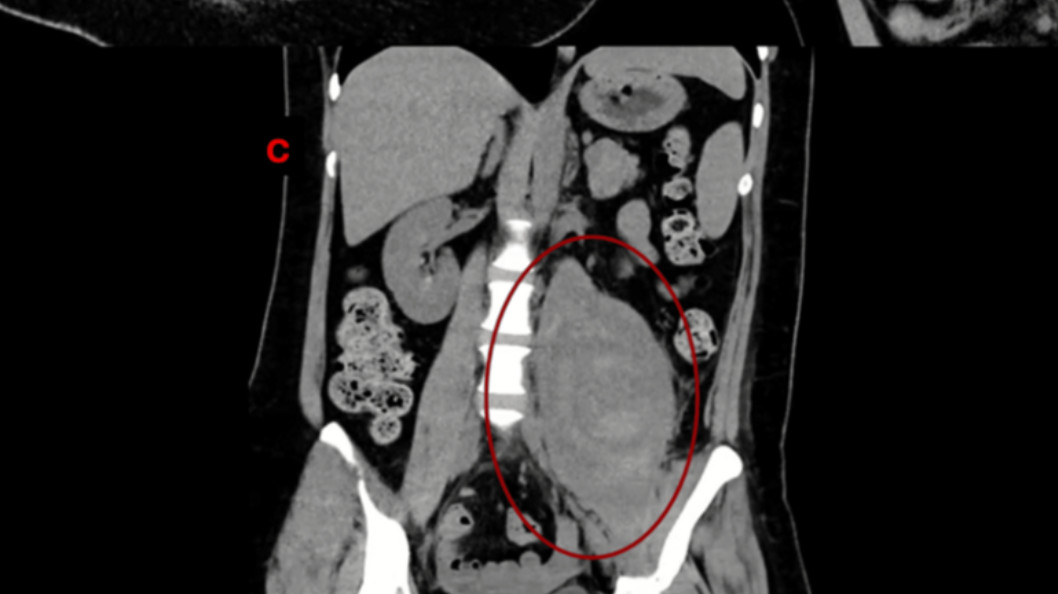

Пациентке провели КТ, МРТ и КТ с контрастом. Была выявлена гематома левой подвздошно-поясничной мышцы объемом 896 мл, сдавливавшая бедренный нерв. Других отклонений не обнаружено. Для дренирования установлен катетер. Спустя три месяца гематома уменьшилась до 257 мл. Боль и слабость в левой ноге разрешались постепенно. Спустя шесть месяцев у пациентки сохранялась парестезия в ноге, боль — 3 из 10 баллов, сила конечности — 4 из 5 баллов. В левой подвздошно-поясничной мышце обнаружена остаточная жидкость объемом 43 мл.